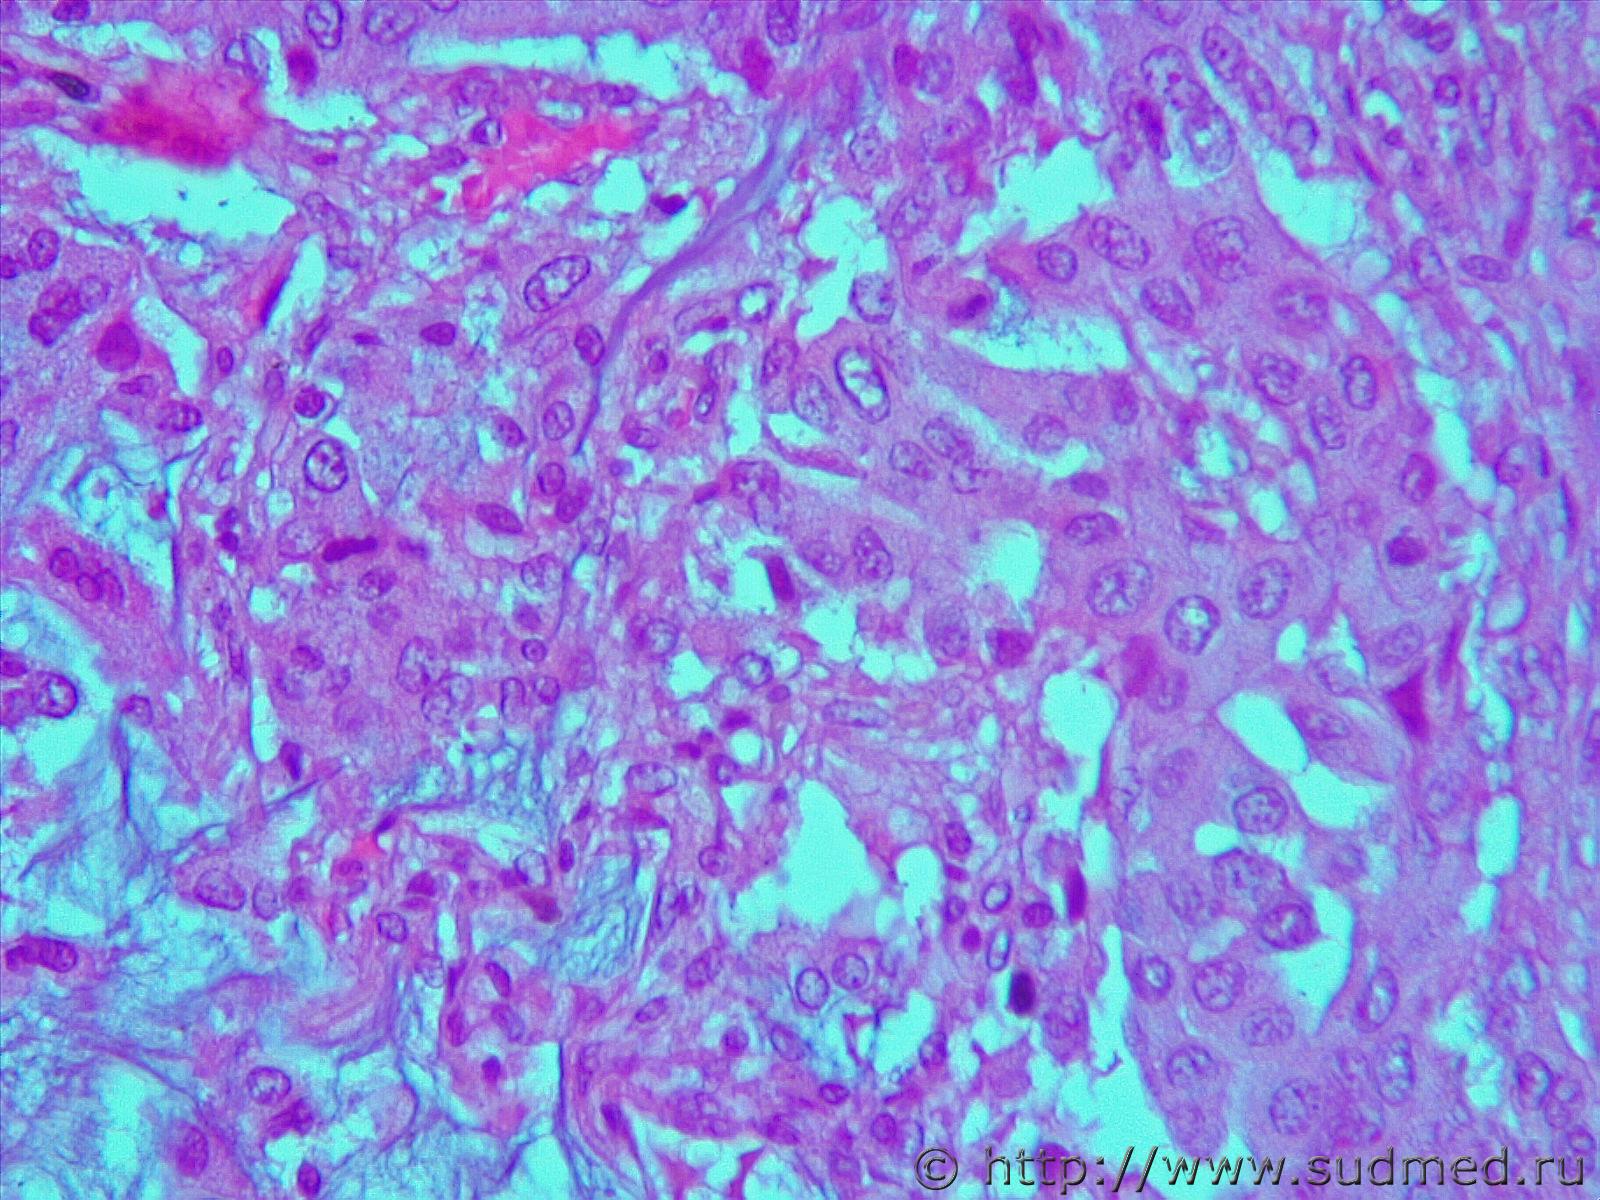

подскажите пожалуйста с опухолью.. совсем туго идет

Могу лишь предположить н/д аденокарциному со слизеобразованием

Фото не увеличиваются, но можно предположить, что это аденокарцинома.